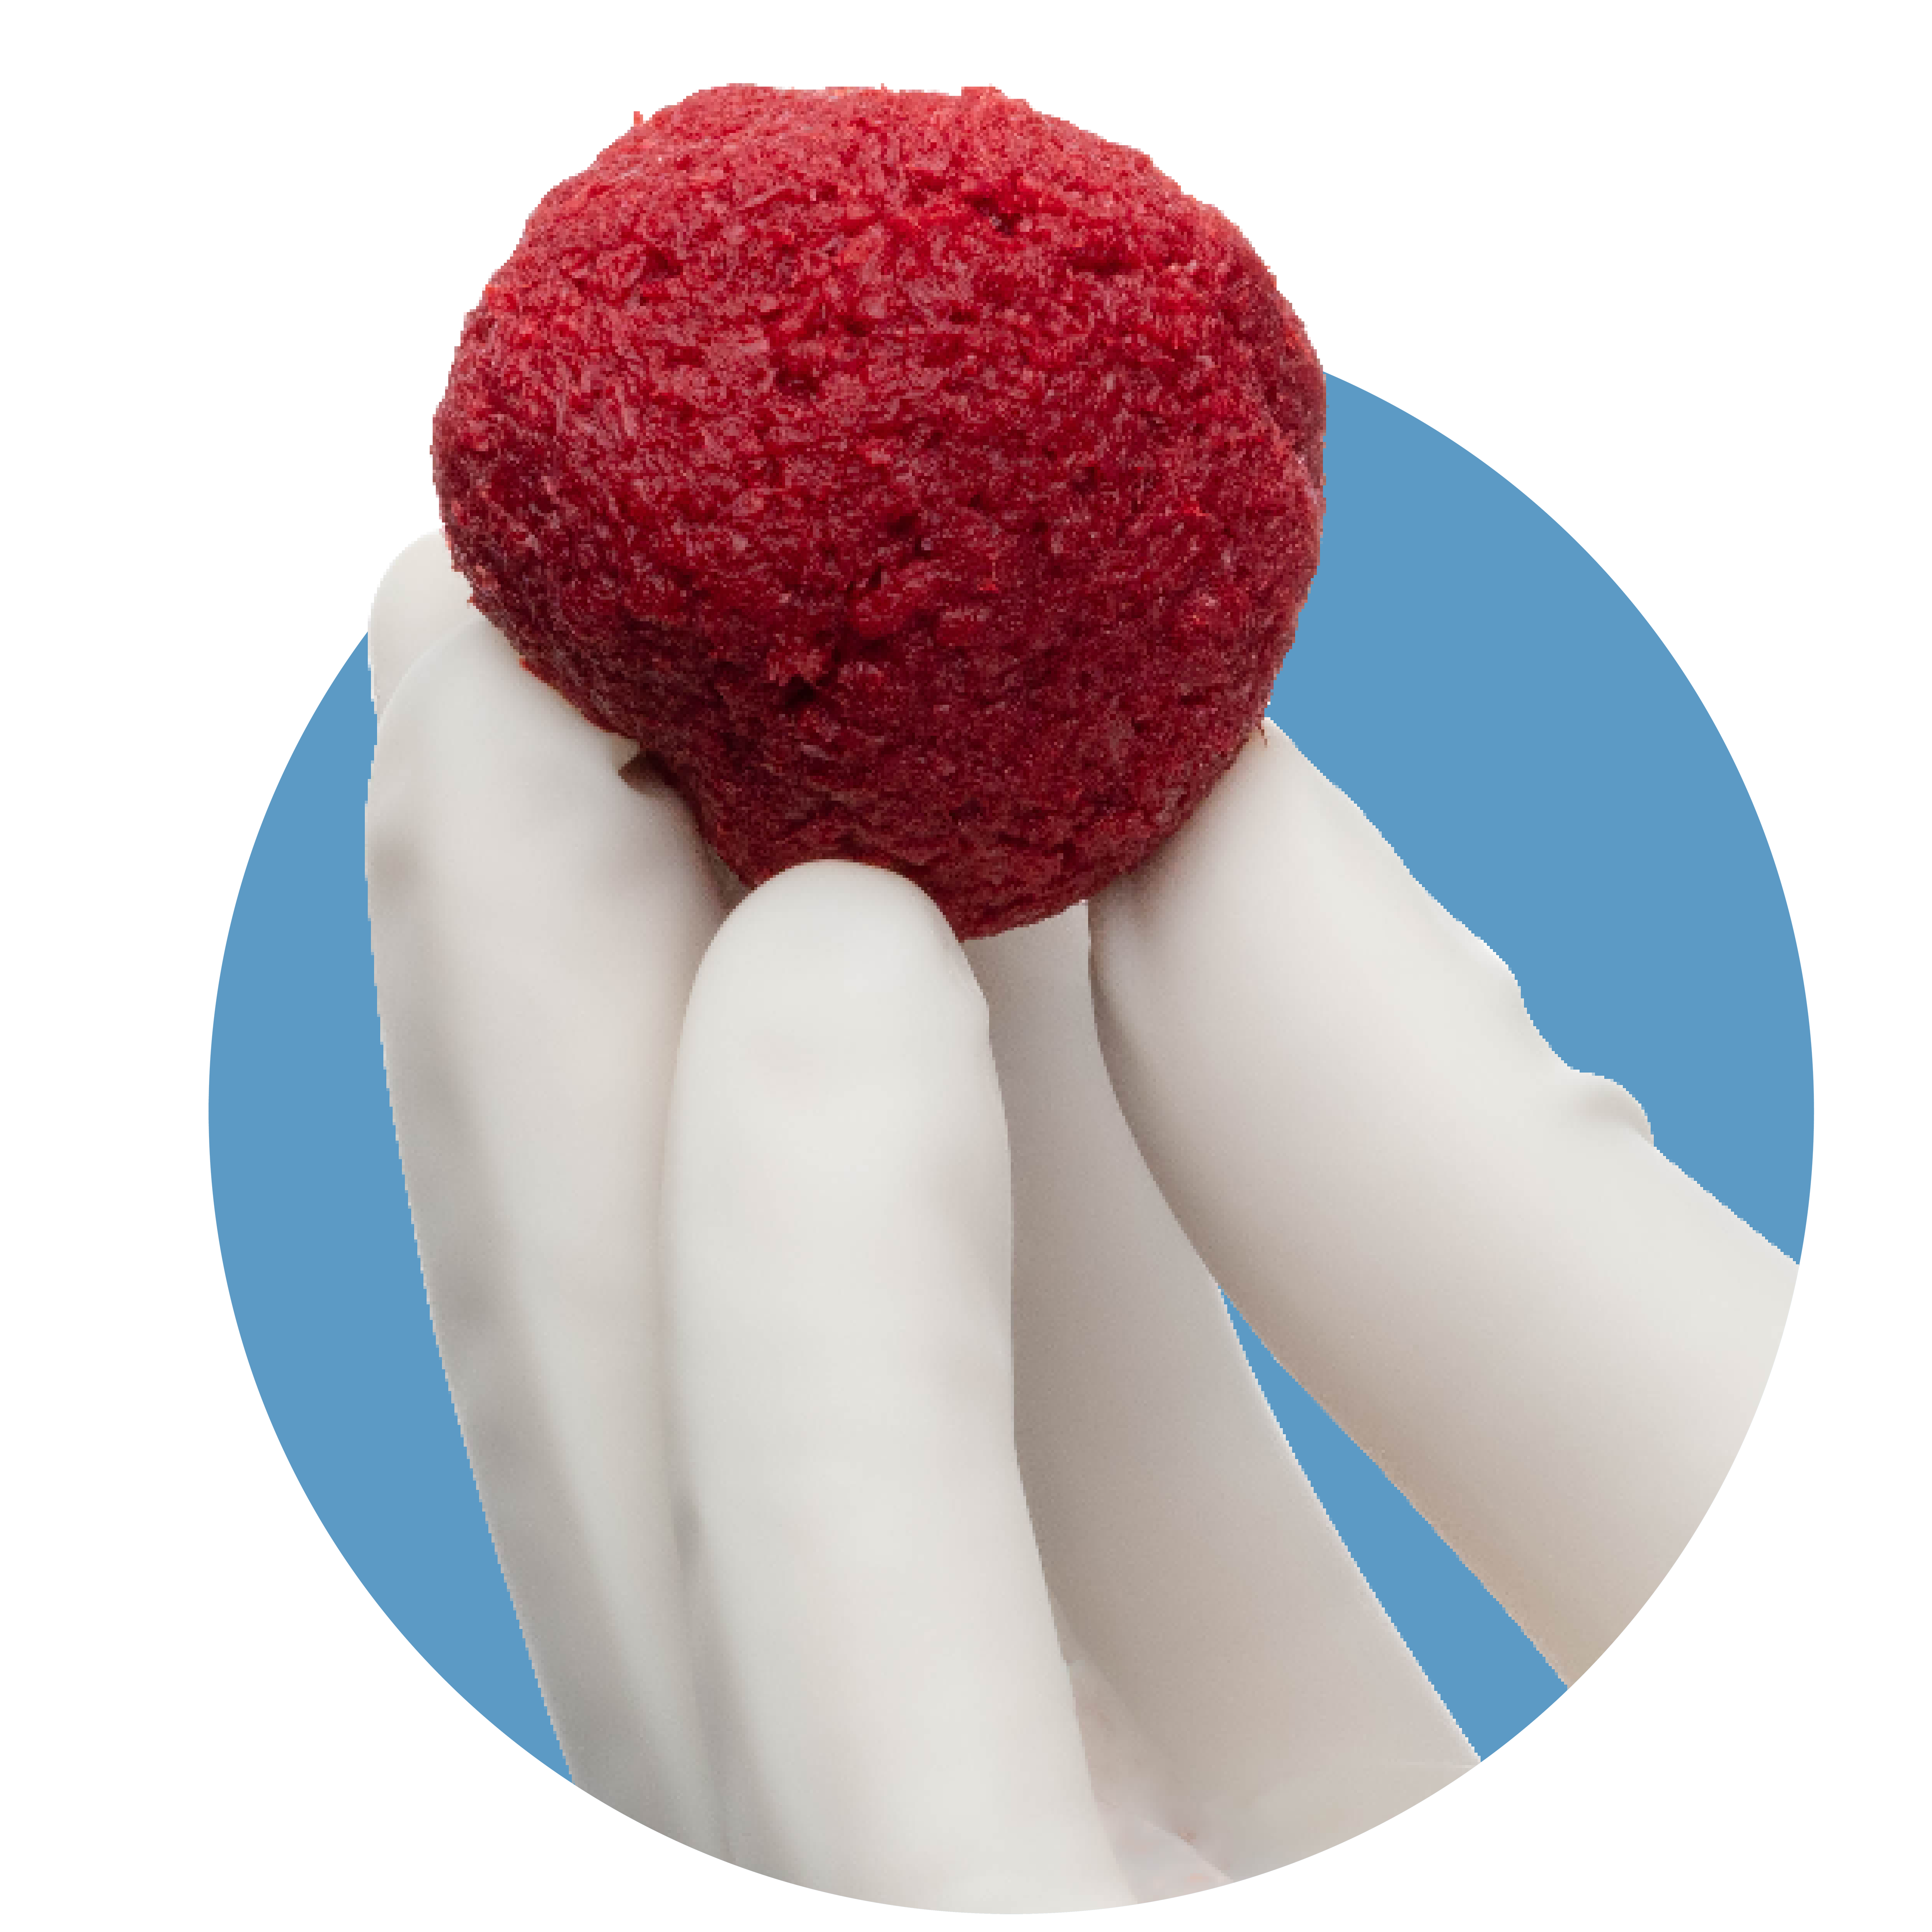

Innovative Surface Technology

The unique surface characteristics of PliaFX fibers set the standard for osseointegration.4-6 With a large surface area and well-structured demineralized cortical fibers, PliaFX provides a solid scaffold that fosters cellular viability and proliferation.4† Our proprietary processing method creates favorable porosity and microhook protrusions, improving the graft's osteoconductivity.4,10†

Scanning electron microscopy (SEM) at 3000x magnification. Images were pseudo colored in Adobe Photoshop to distinguish the cells (in yellow) from the fibers.

Optimized Handling

The interlocking fiber microhooks in PliaFX grafts provide optimized handling characteristics.4,5,7,8† The fibers interlock to provide a moldable, intact graft that easily transfers to the surgical site, conforms to the surgical site, and resists migration.4